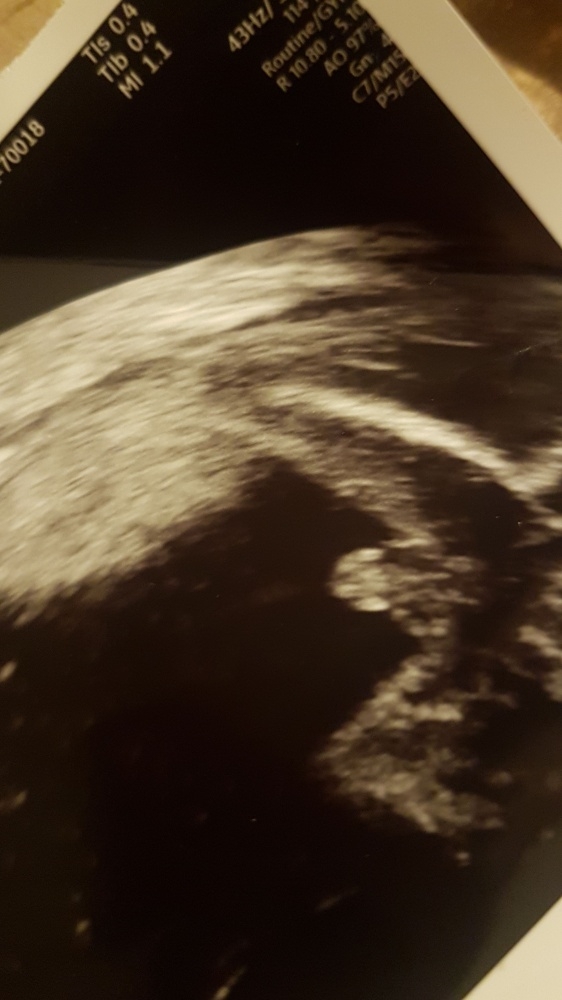

Allerdings traue ich mich immer noch nicht einkaufen zu gehen weil das Bild mich stutzig macht, hab nichts vergleichbares im Internet gefunden 🤔

• zs2sjpg4tads.jpeg

Anbei sende ich euch mal ein Foto :)

• @Julizie das ist ein sehr zeigefreudiger Junge! War mein Sohn übrigens auch und das US Bild sah genau so aus

• Eindeutig Junge 😂

In der 18. Woche hingegen kann man das Geschlecht schon ziemlich sicher bestimmen. Und bei dem von dir gezeigten Bild, würde ich fest davon ausgehen, dass es beim Jungen bleibt. :D

Wenn ein Knirpsi nicht so zeigefreudig ist, kann man einen Penis schon mal übersehen. Aber in eurem Fall ist er ziemlich unübersehbar und ich halte eine Täuschung da für praktisch ausgeschlossen.